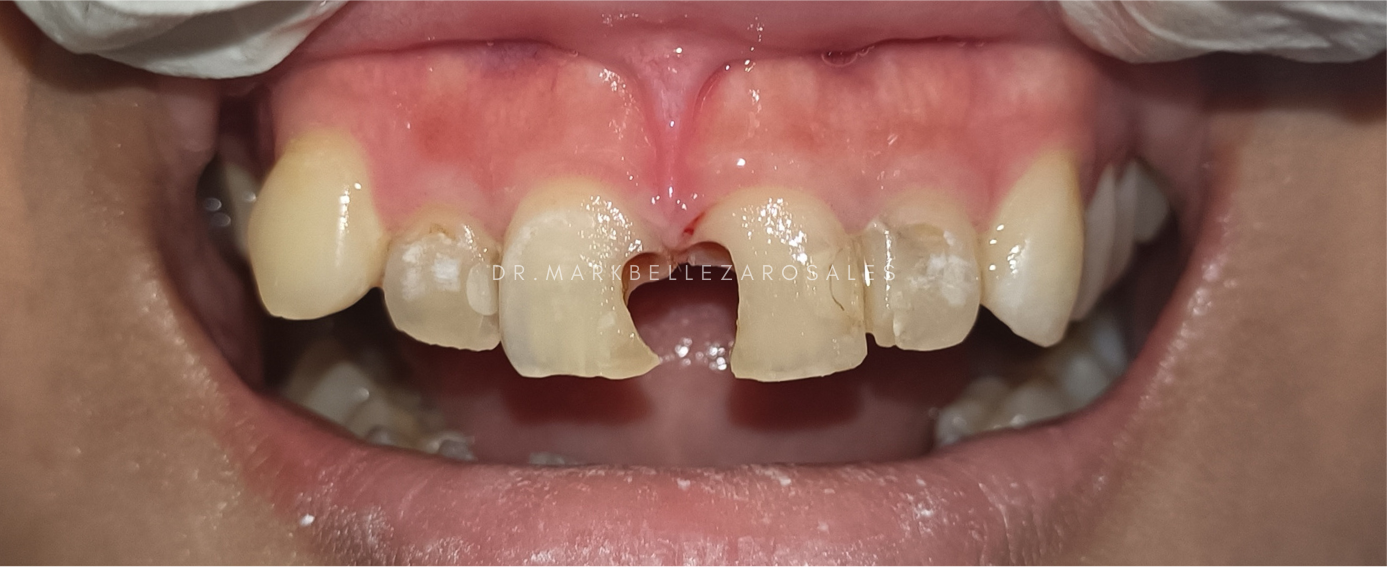

Composite restoration is a tooth-colored dental filling used to repair cavities, chips, or damaged teeth. It blends naturally with the tooth, restores strength and function, and is typically completed in a single dental visit.